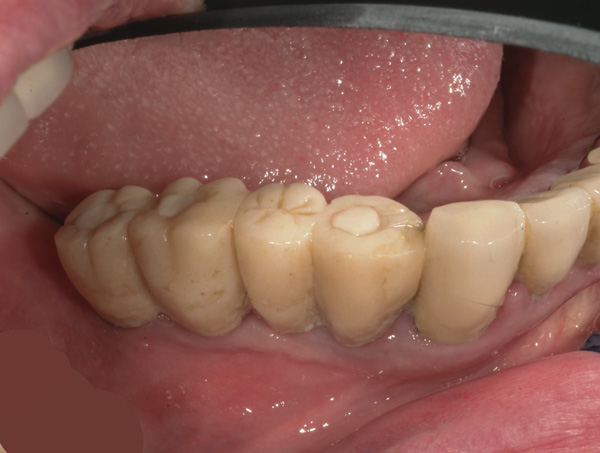

Background: In this case, the patient had a failing mandibular and maxillary dentition due to caries secondary to radiation-induced xerostomia. The patient had had a radical neck dissection to remove a squamous cell carcinoma of the throat 9 years prior to his prosthodontic consultation with the authors. The patient reported a history of radiation therapy following surgery, but did not have a shielding stent. A staged approach was used so as to avoid removable prosthetics on his severely dry soft tissues. He chose to treat his mandibular issues first. Figure 9 shows healing abutments next to the temporarily retained natural teeth, and Figure 10 shows the first-stage custom abutments inserted with relatively good gingival contour and no recession. Recession was clearly seen around all first-stage abutments following adjacent extractions and second-stage implant placement (Figure 11).

Figure 9 Healing abutments.

Figure 9

Figure 10 First-stage custom abutments.

Figure 10

Figure 11 Recession evident around first-stage abutments following adjacent extractions and second-stage implant placement.

Figure 11